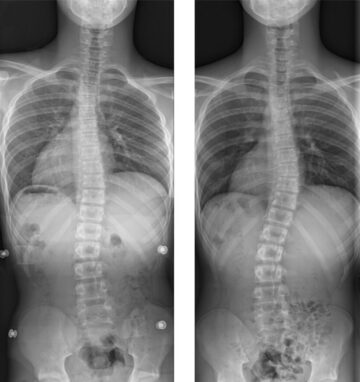

كم يستغرق علاج اعوجاج العمود الفقري ومتى يصل طفلك للشفاء التام؟ دليل مبسط للأهالي اعوجاج العمود الفقري، المعروف طبياً باسم Scoliosis، من أكثر الحالات التي تثير قلق الأهالي والمرضى، خاصة عند طرح السؤال الشائع:

كم تستغرق مدة علاج اعوجاج العمود الفقري؟ عند تشخيص الطفل أو المراهق بـ اعوجاج العمود الفقري (الجنف)، يتساءل كثير من الأهل:كم تستغرق مدة علاج اعوجاج العمود الفقري؟ وهل يمكن تحديد فترة معينة؟هذا السؤال شائع

كم تستغرق مدة العلاج بحزام اعوجاج العمود الفقري؟ عند تشخيص الطفل أو المراهق بـ اعوجاج العمود الفقري، يبدأ القلق فورًا، ويظهر سؤال أساسي ومهم: كم تستغرق مدة العلاج بحزام اعوجاج العمود الفقري؟ وهل يمكن